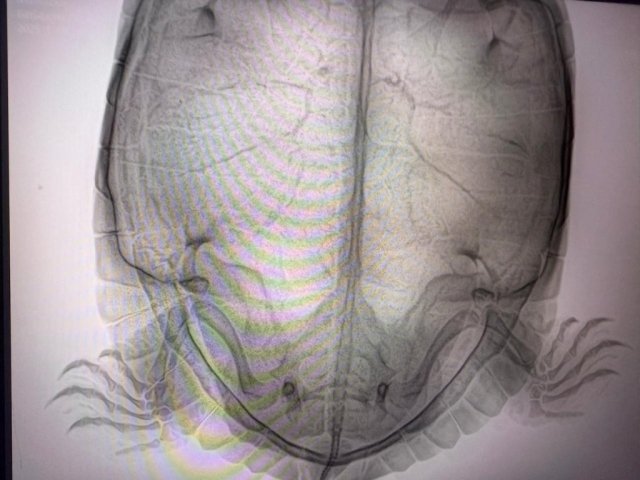

9.Обращались ли в ветклинику? Как называется ветклиника? Как зовут врача (ФИО)? Вводились ли какие-то препараты, если да, то в каких дозировках? Что было сделано по рекомендациям врача? Герпетологов в городе нет, делали рентген, яйца есть.

22a7d346-fe2c-41b3-834c-e9f7e0750714.JPG

@moth 17.01 после курса уколов черепаха снесла 10 яиц, хотя на первоначальном снимке их было 7.

18.01 сделали контрольный снимок, на снимке оставшихся яиц не видно, либо рентген слишком мощный и он просветил все насквозь.